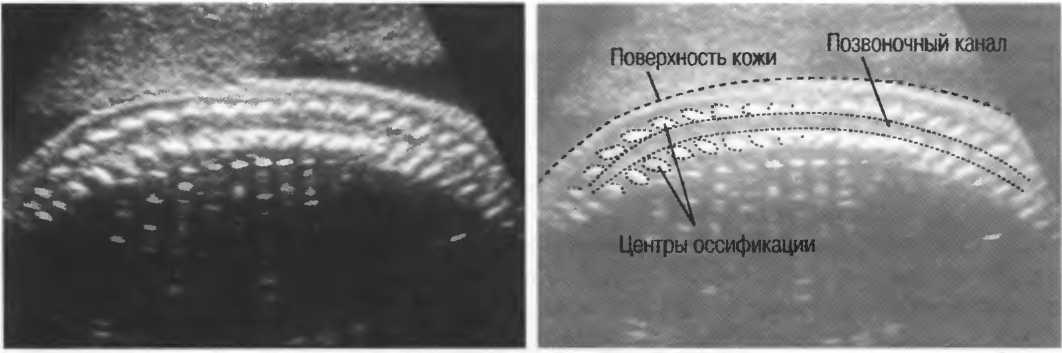

Рис.5. Два поперечных среза плода, демонстрирующих тень от позвоночника плода. Аналогичная тень от ребер может частично закрывать почки или печень. Изменяя угол наклона датчика, можно изменить положение тени таким образом, чтобы подлежащие ткани были видны отчетливо.